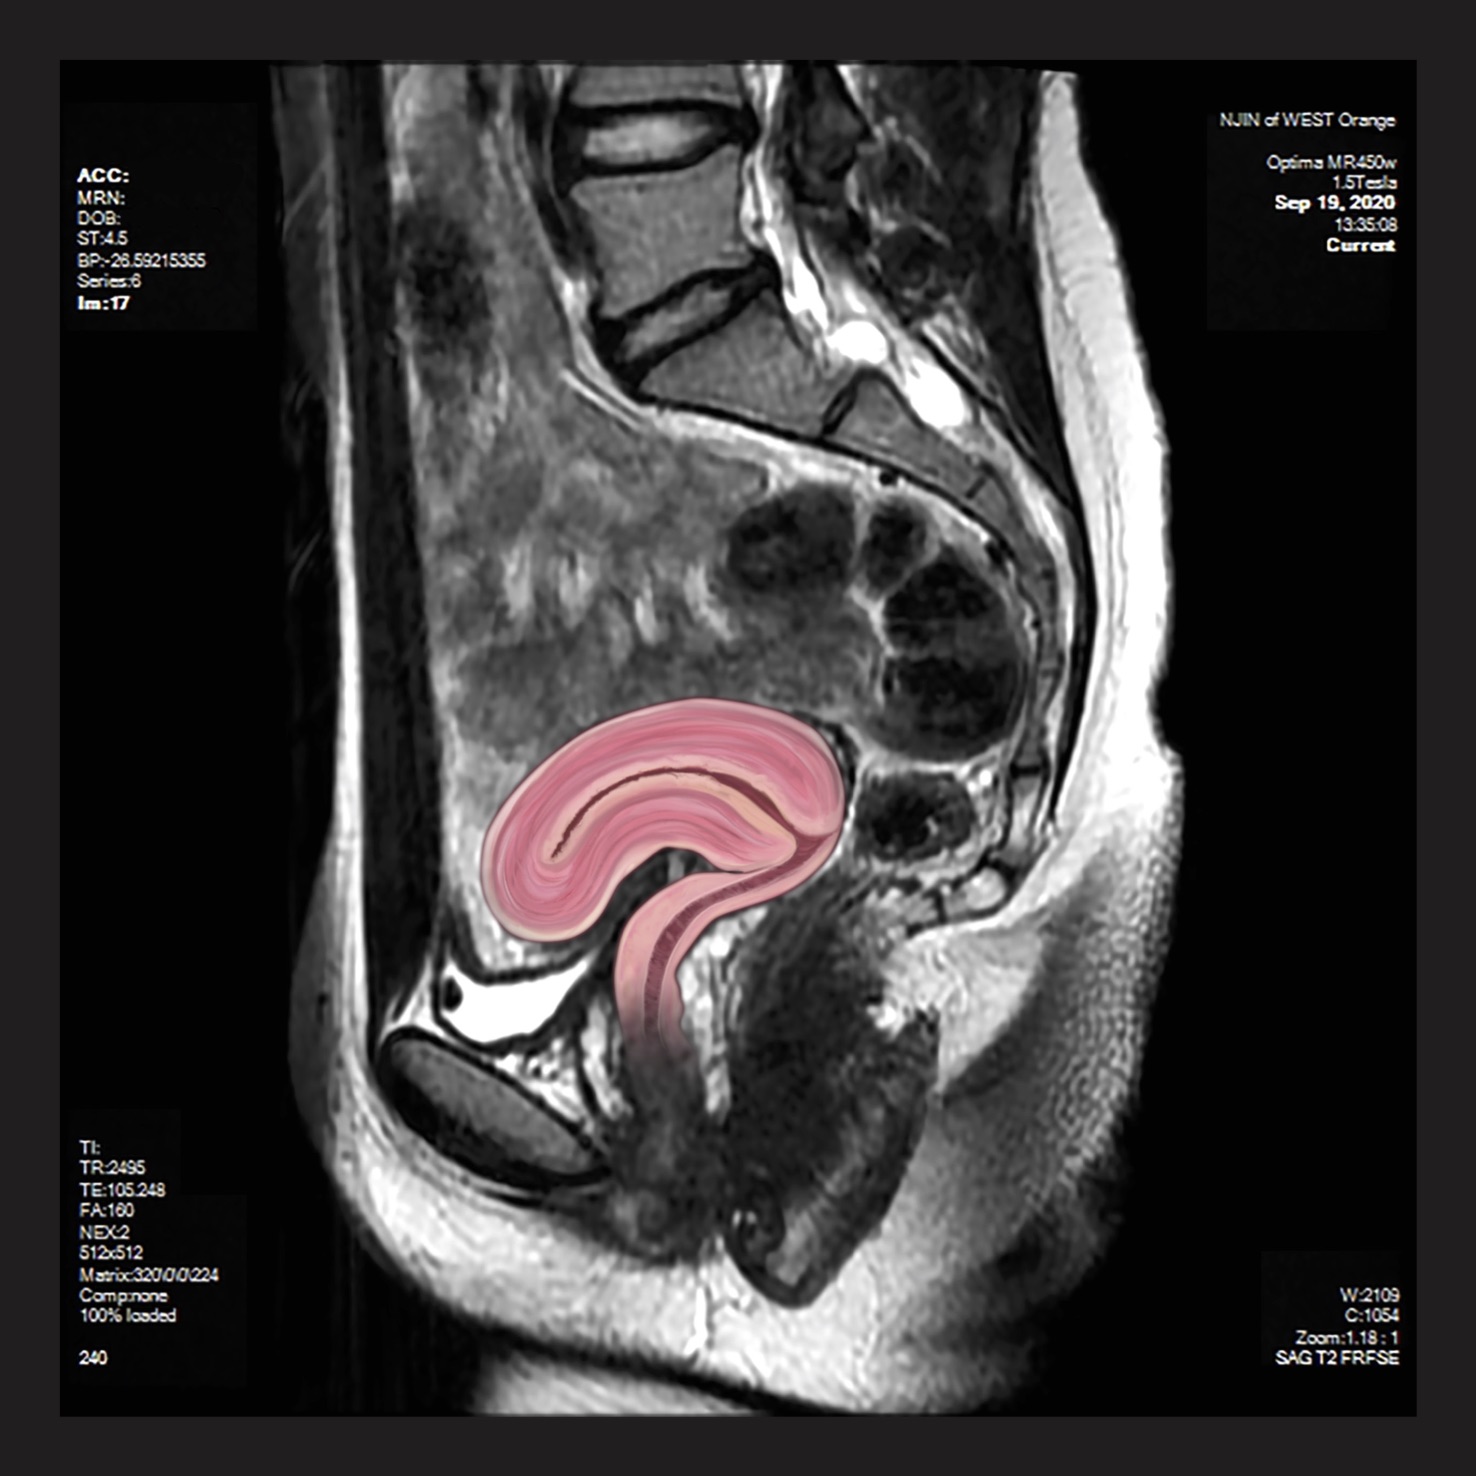

CT scans, MRIs, and X-Rays are all, in a way, portraits of the patient. Films that result from a diagnostic exam display information that is deeply intimate by nature but is often incomprehensible to the patient. The patient learns about themselves and their condition, whether chronic or newly diagnosed, from the words of their physician. Someone without any medical training sees themself as a series of black, white, and gray shapes on a computer screen or printed out on a film. Flesh and bone are abstracted in a way that disconnects them from the body which they represent.

This abstraction and disconnection creates a complicated encounter – how does one relate to an image of themselves when, from their perspective, it looks like little more than television static?

In instances like this where an artist is given a prompt, platform, and permission to create, it is possible to unify select individuals with their films. A patient is elevated to an individual human being by linking a face, name, and snippets of their personality with what would otherwise be a diagnostic assessment reserved for the eyes of physicians. This exhibition is about connecting the individual to themselves and others, and furthering the integration of art and science. Disclosure aims to dignify a patient and their condition through a work of art, and bridge the gap between the results of a diagnostic medical exam and what makes us human.